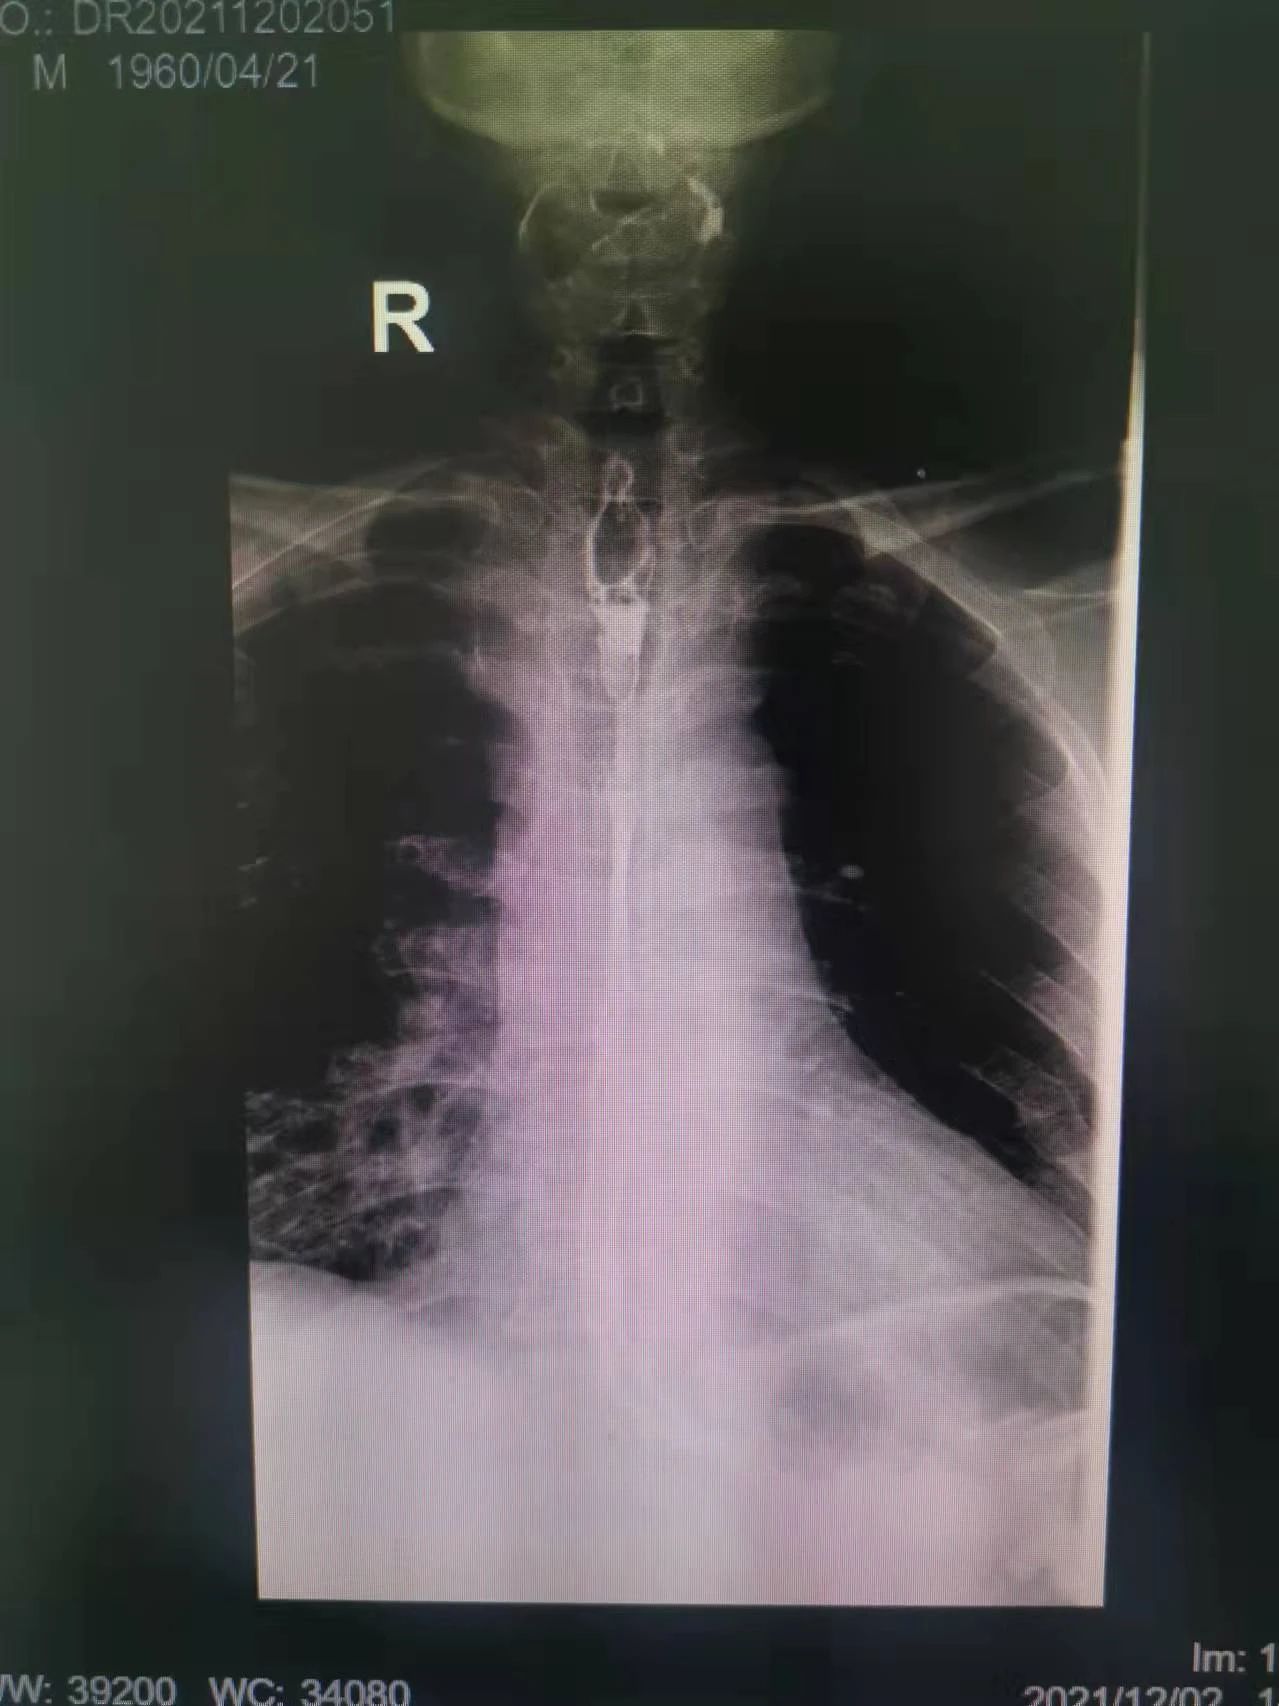

在這種情況下,我院介入二科侯主任決定通過介入治療中的食管支架植入來幫助患者實(shí)現(xiàn)這個(gè)愿望。手術(shù)當(dāng)日,侯主任在機(jī)器的幫助下,將一根細(xì)細(xì)的導(dǎo)絲穿過腫瘤到達(dá)付大爺胃部,然后再沿著導(dǎo)絲,把壓縮好的支架放在腫瘤里面。通過后撤導(dǎo)管,把壓縮的支架打開,支架把腫瘤撐開,讓食管不再堵塞。有了支架的支撐,付大爺就可以自由地吃東西了,哪怕食管和氣管有溝通,因?yàn)橹Ъ芨采w了腫瘤,通道堵住了,吃的東西也不會(huì)吸到肺內(nèi)造成感染。這時(shí)痛痛快快地吃上一頓,也不再是奢望!

手術(shù)很順利,付大爺也在術(shù)后第2天喝到了自己日思夜想的清水,露出了久違的笑容。從某種意義上講,介入食管支架置入術(shù)的成功實(shí)施,付大爺不能進(jìn)食的病已經(jīng)“治好”了,雖然從生理角度來說,付大爺可以通過終生使用腸內(nèi)營(yíng)養(yǎng)來維持生存,但我們所做的是致力于給予患者更好的生存體驗(yàn),或者說是尊嚴(yán)。銘記并保持一名醫(yī)者的初心,我們要做的正如那句著名的墓志銘所說:有時(shí)去治愈,常常去幫助,總是去安慰。